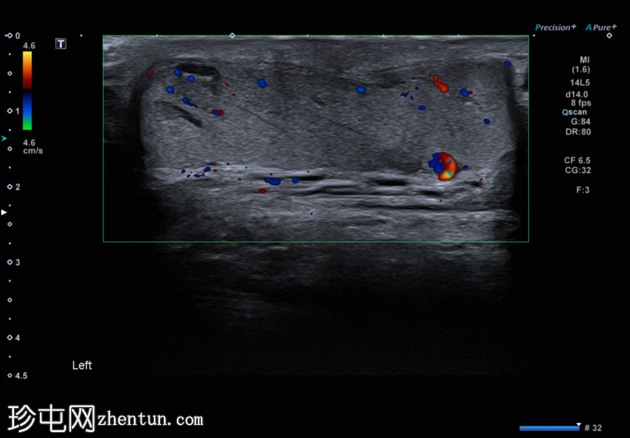

患者既往有睾丸内精索静脉曲张病史,现左侧睾丸

加剧。既往有儿童时期左侧睾丸固定术史。

左侧睾丸内血管呈迂曲管状扩张,Valsalva动作可见充血。

典型的管状睾丸内精索静脉曲张超声表现,Valsalva动作可见扩张的睾丸内静脉充血。睾丸内精索静脉曲张常与同侧儿童时期睾丸固定术相关,本例患者即曾接受过该手术,且多见于左侧,本例亦属如此。